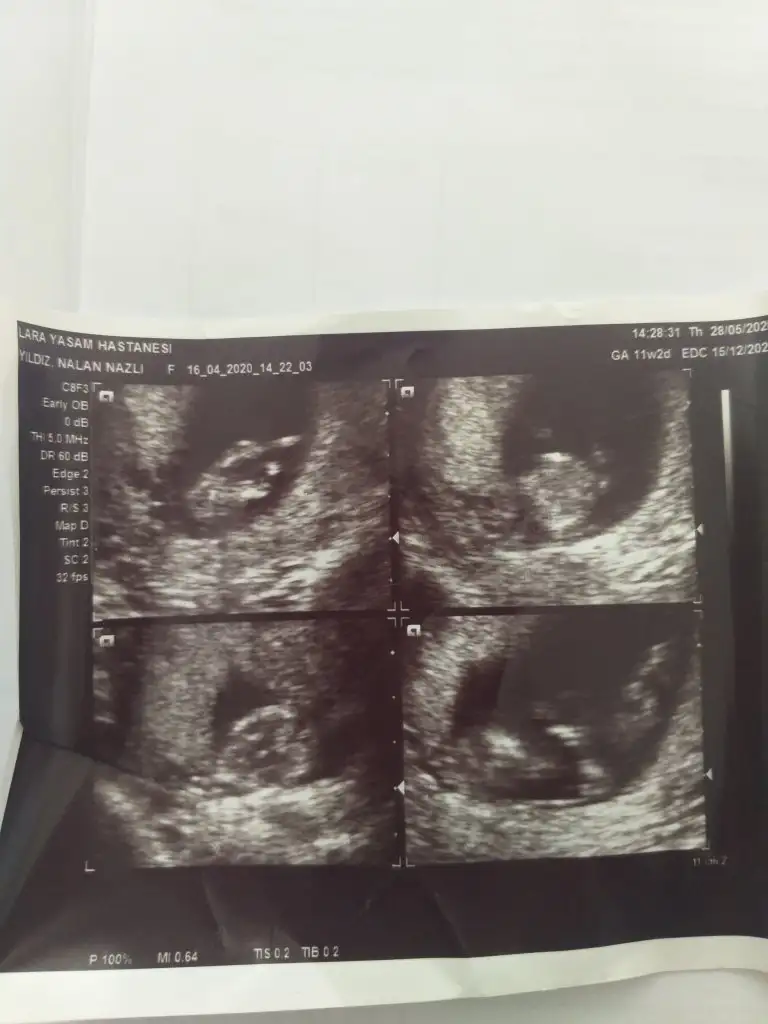

Arkadaşlar 11 hafta 3 günlük hamileyim rica etsem cinsiyet tahmini yapabilir misiniz? Resim ekleyememişim şimdi ekledim şimdiden teşekkürler![]()

P pembemum Konu sahibine yazdım benŞimdilik kız gibi sanki 12-13 haftasınıda paylaşın

kıza benziyor.Arkadaşlar 11 hafta 3 günlük hamileyim rica etsem cinsiyet tahmini yapabilir misiniz? Resim ekleyememişim şimdi ekledim şimdiden teşekkürler![]()

Erkek onun bebegi yazıştık biz 13 haftasında erkek demiş dr bende 11 haftasında erkek tahmin etmiştim onun gönlü kız istiyordu umarım 16 haftada dr kız der

Yaa hayırlı saglıklı olsunErkek onun bebegi yazıştık biz 13 haftasında erkek demiş dr bende 11 haftasında erkek tahmin etmiştim onun gönlü kız istiyordu umarım 16 haftada dr kız der12+6 usg sinde nubu tam karşıya bakıyordu tam dikte değil paralelde değil ama dr %80 erkek demiş